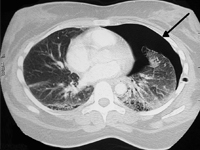

ChirurgiaWprowadzenie antybiotyków, masowe szczepienia mające na celu zapobieganie chorobom zakaźnym oraztransplantacje narządów można uznać za największe osiągnięciamedycyny XX wieku. Przeszczepy narządów litych ratują życie pacjentom dotkniętym niewydolnością narządową oraz poprawiają jakość ich życia. Długośćżycia pacjentów po przeszczepach uległa znacznej poprawie w ciągu dwóch ostatnich dekad. Skuteczne przeszczepienie zwiększa przeżywalność u chorych przewlekle dializowanych oraz u pacjentów z nieodwracalnymi chorobami wątroby, serca i płuc i schyłkową niewydolnością tych narządów. Odsetek wykonywanych transplantacji stale rośnie, ale wciąż jest niewystarczający [1]. Zgodnie z danymi zgłoszonymi do Global Observatory on Donation and Transplantation (GODT), w 2010 roku w 95 krajach świata wykonano 106 879 przeszczepień organów w tym:73 179 przeszczepów nerek (46% od żywych dawców), 21 602 przeszczepów wątroby (15% od żywych dawców), 5582 przeszczepów serca, 3927 przeszczepów płuc, 2362 przeszczepów trzustki i 227 przeszczepów jelita cienkiego. Aktywność ta wzrosła o 2,12% w stosunku do 2009 roku [2].Niestety szacuje się, że liczba wykonywanych przeszczepów jest niewystarczająca. Jednocześnie istnieją ogromne różnice geograficzne w zakresie liczby przeszczepieńprzypadających na milion mieszkańców: od 70 na milion mieszkańców w krajach rozwiniętych do 0-2,4 w krajach rozwijających się [3]. W związku z tym, że transplantacja przedłuża życie pacjentów, nowotwory stają się coraz większym zagrożeniem dla długotrwałego przeżycia, zwłaszcza u pacjentów po przeszczepieniu wątroby z powodu raka wątrobowokomórkowego (ang. hepatocellular carcinoma, HCC)[4].Ryzyko wystąpienia nowotworów u osób poddanych transplantacji jest wyższe niż w ogólnej populacji. Wynika to z trzech przyczyn. Leczenie immunosupresyjne towarzyszące przeszczepianiu narządów powoduje spadek odporności, który może sprzyjać zakażeniu wirusami onkogennymi jak np. HPV (ang. humanpapillomavirus) czy HHV-8 (ang. humanherpesvirustype 8) oraz może umożliwić ucieczkę powstających komórek nowotworowych spod osłabionego nadzoru immunologicznego. Ponadto leki immunosupresyjne działają cytotoksycznie, co może indukować powstanie mutacji i przekształcanie prawidłowych komórek w komórki nowotworowe. Dlatego też u chorych poddanych przeszczepianiu narządów najczęściej rozwijają się nowotwory hematoonkologiczne, nowotwory związane z infekcją potencjalnie onkogennymi wirusami: mięsak Kaposiego (infekcja ludzkimi wirusami herpes), rak szyjki macicy i płaskonabłonkowe raki regionu głowy i szyi (infekcja wirusem brodawczaka ludzkiego), rak wątroby (infekcja wirusami zapalenia wątroby typu B i C) oraz nowotwory skóry. Rak płuca, nowotwory przewodu pokarmowego lub układu moczowego występują nie częściej niż u 1% osób poddawanych transplantacji. Możliwość zastosowania leczenia systemowego nowotworów u chorych po przeszczepie narządów musi zostać jeszcze zbadana. Największe kontrowersje budzi stosowanie immunoterapii u chorych na nowotwory poddanych wcześniej przeszczepom narządów i leczeniu immunosupresyjnemu. Współczesne metody immunoterapii chorób nowotworowych ukierunkowane na immunologiczne punkty kontroli mają za zadanie wzmocnić odpowiedź immunologiczną, a tym samym mogą zwiększyć ryzyko odrzucenia przeszczepu. Rak płuca jest jedną z głównych przyczyn zgonów z powodu nowotworów złośliwych na całym świecie. Istnieją dwa główne typy raka płuca: niedrobnokomórkowy rak płuca (NDRP) i drobnokomórkowy rak płuca (DRP). NDRP występuje znacznie częściej, stanowiąc 80-85% przypadków raka płuca. W leczeniu raka płuca zastosowanie znalazły zabiegi torakochirurgiczne, chemioterapia oraz radioterapia [5]. W związku z niezadawalającymi wynikami leczenia zaczęto poszukiwać nowych sposobów terapii. Przełomem okazało się zastosowanie immunoterapii oraz terapii ukierunkowanych molekularnie. Metody te z powodzeniem są stosowane u wybranych chorych na miejscowo zaawansowanego i przerzutowego NDRP. Terapie te doprowadziły do wydłużenia czasu wolnego od progresji choroby oraz całkowitego czasu przeżycia pacjentów, co pozwoliło zakwalifikować raka płuca do choróbprzewlekłych [6].